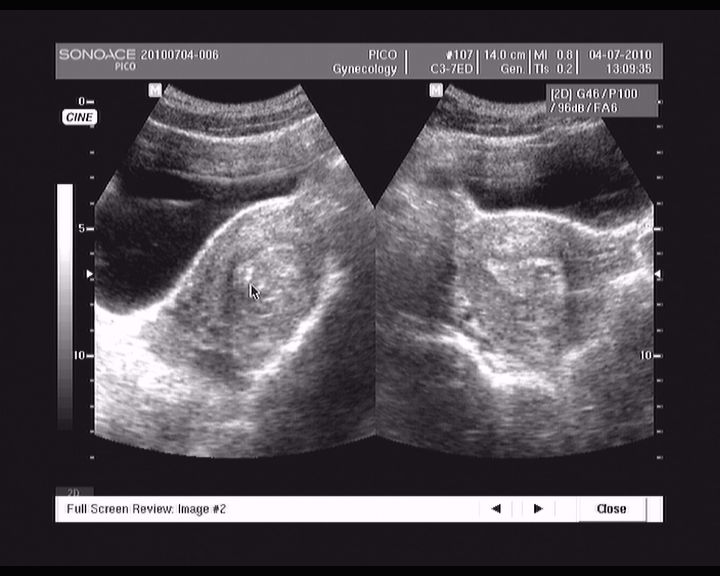

abrasio 01.07.2010

11.jpg